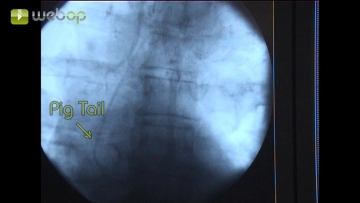

Um eine zentrale DSA und Markierung des Abgangs von Arteria subclavia und Truncus coeliacus zu gewährleisten Einbringen einer 6F-Schleuse über die freigelegte Arteria brachialis links in Seldinger-Technik. Über die Schleuse Einführen eines Terumo®-Drahts. Lokale Gabe von 2000 IE Heparin-Kochsalz-Lösung.

Nach Einbringen der relativ starren endoluminalen Aortenprothese zusammen mit dem Trägersystem können die Markierungen jedoch gelegentlich von der tatsächlichen Position der Marker abweichen. Bei knappen Distanzen zwischen Prothesenende und Arteria subclavia bzw. Truncus coeliacus wie im Filmbeispiel ist eine erneute DSA vor Freisetzen des Prothesenkörpers erforderlich, damit die Lumina der vorgenannten Gefäße nicht versehentlich verlegt werden.